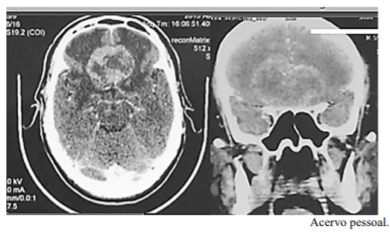

Considere um paciente de 59 anos de idade, com 90 kg, hipertenso e tabagista. Ele é levado ao hospital por familiares em razão de cefaleia persistente e progressiva. Os familiares relatam, ainda, alteração de comportamento há aproximadamente dois meses, associada à diminuição global de força. Ao exame, o paciente está pouco colaborativo, irritado, com fala inapropriada e hiposmia, sem deficits focais ao exame. Constatam-se AC = RC2T com BNF; FC = 82 bpm; AP = MVF sem RA; FR = 18 irpm; PA = 150 mmHg x 85 mmHg; e SatO2 = 97%. É realizada a tomografia computadorizada (TC) de crânio, conforme a imagem apresentada.